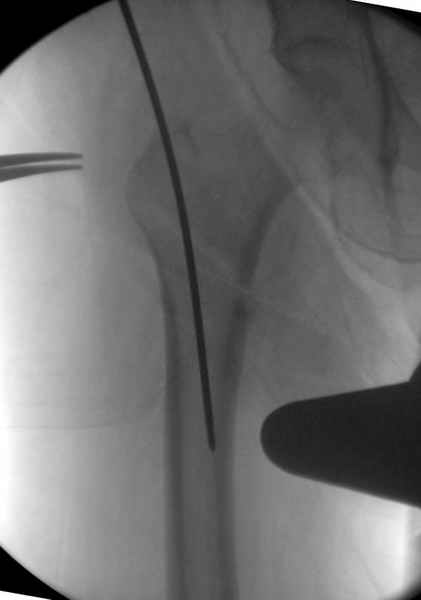

Мы получили испытательный вариант инструментария для пробы, хотя компания объявила, но ещё не для широкой публики, обещают к сентябрю. За полтора месяца, включая сегодняшнюю, вот уже восьмая операция по счету. Удобный инструментарий, ничего лишнего, научились делать быстро, посмотрим что будет, пока нравится.

Все больные пожилого возраста, первые уже успели появиться на амбулаторном приеме, пока без осложнений.

Здесь сканнированные снимки импланта и операционные снимки больной.

На этом снимке процесс компрессии нижним болтом.

Итог